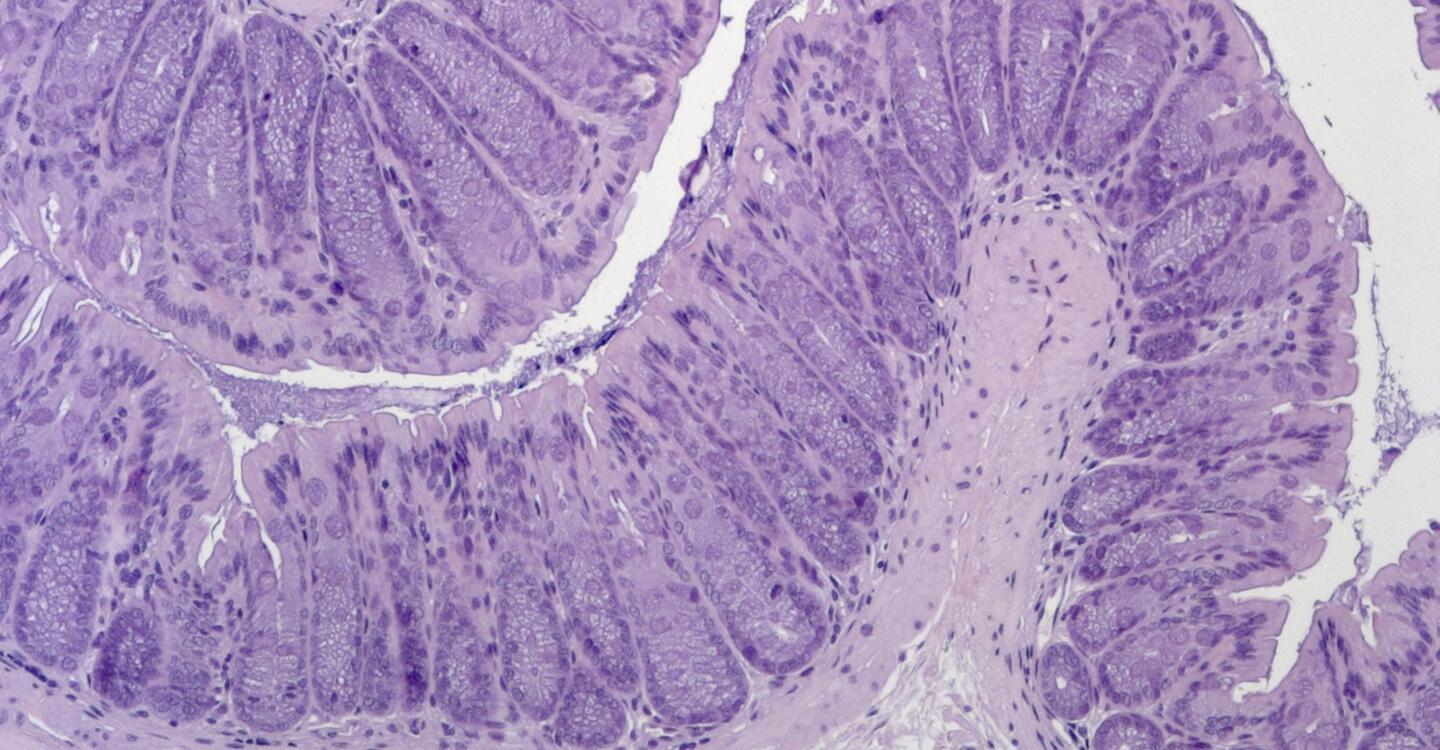

Das Bild zeigt Darmgewebe aus einem Mausmodell für die erworbene generalisierte Lipodystrophie. Das Gewebe blieb auch nach der Behandlung mit einer Chemikalie, die normalerweise eine Darmentzündung auslöst, intakt.